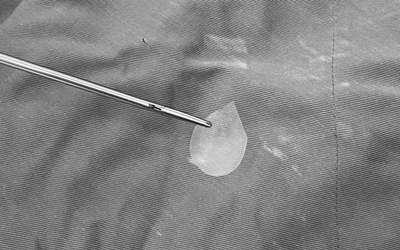

Bé 1 tuổi nhập viện trong tình trạng đau đớn, bác sĩ gắp ra thứ "đáng sợ" trong bụng

Tại khoa Cấp cứu, các bác sĩ tiến hành thăm khám và nội soi khẩn cấp. Kết quả cho thấy cây kim băng đã bung ra hình chữ L., đầu nhọn ghim vào thành thực quản gây nguy cơ thủng, xuất huyết và nhiễm trùng nặng.